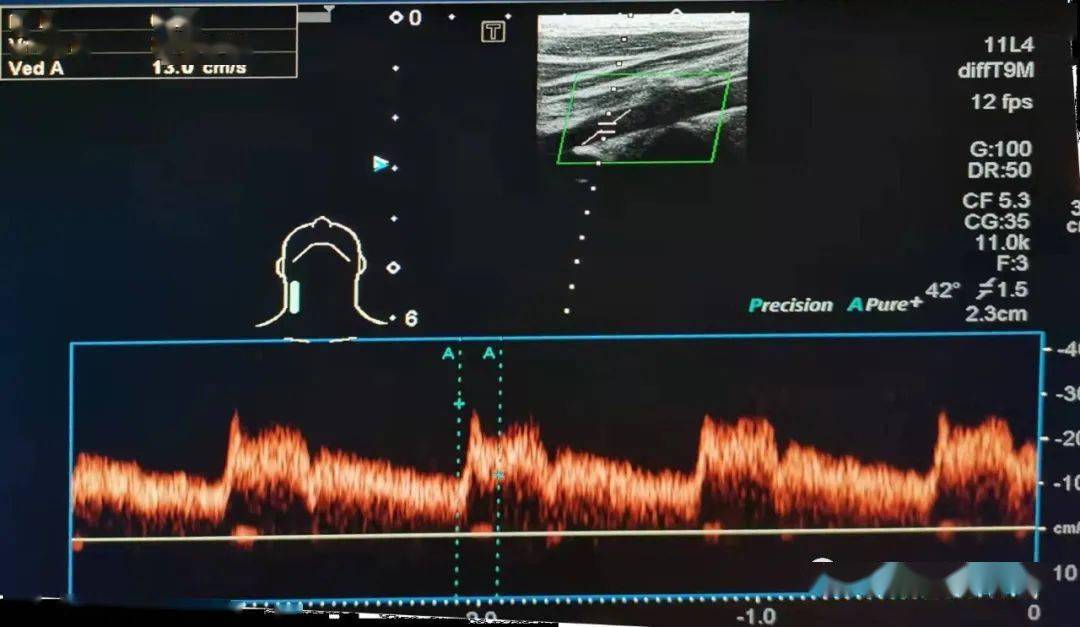

血管超声问答61这个椎动脉双向频谱是部分窃血吗

图片尺寸1080x627